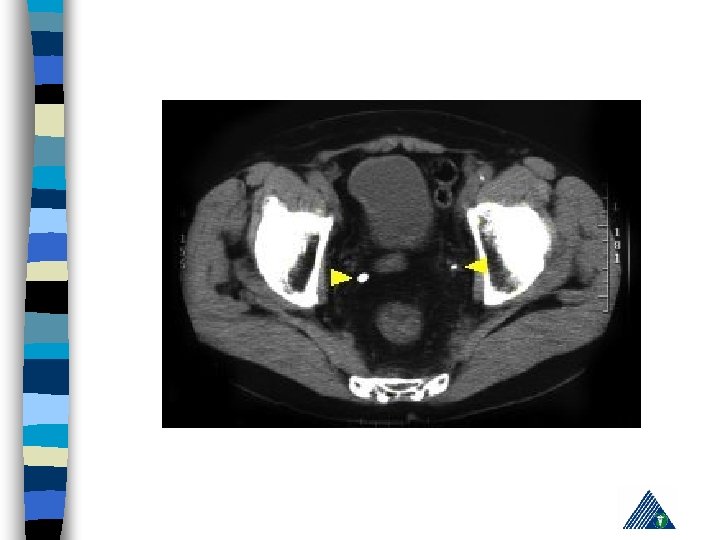

R: Appendicitis - Cholelithiasis n urinalysis: hematuria n KUB n IVP n Computerized Tomography n Pain management, hydration, hot bath n Treatment of the underlying cause n

Radiologic Imaging n n n KUB (loss of psoas or renal contour) IVU (delayed renal function, nonhomogenous collecting system) USG (lumbar hematoma and urinoma lokalizasyonu) Computerized Tomography Renal angiography